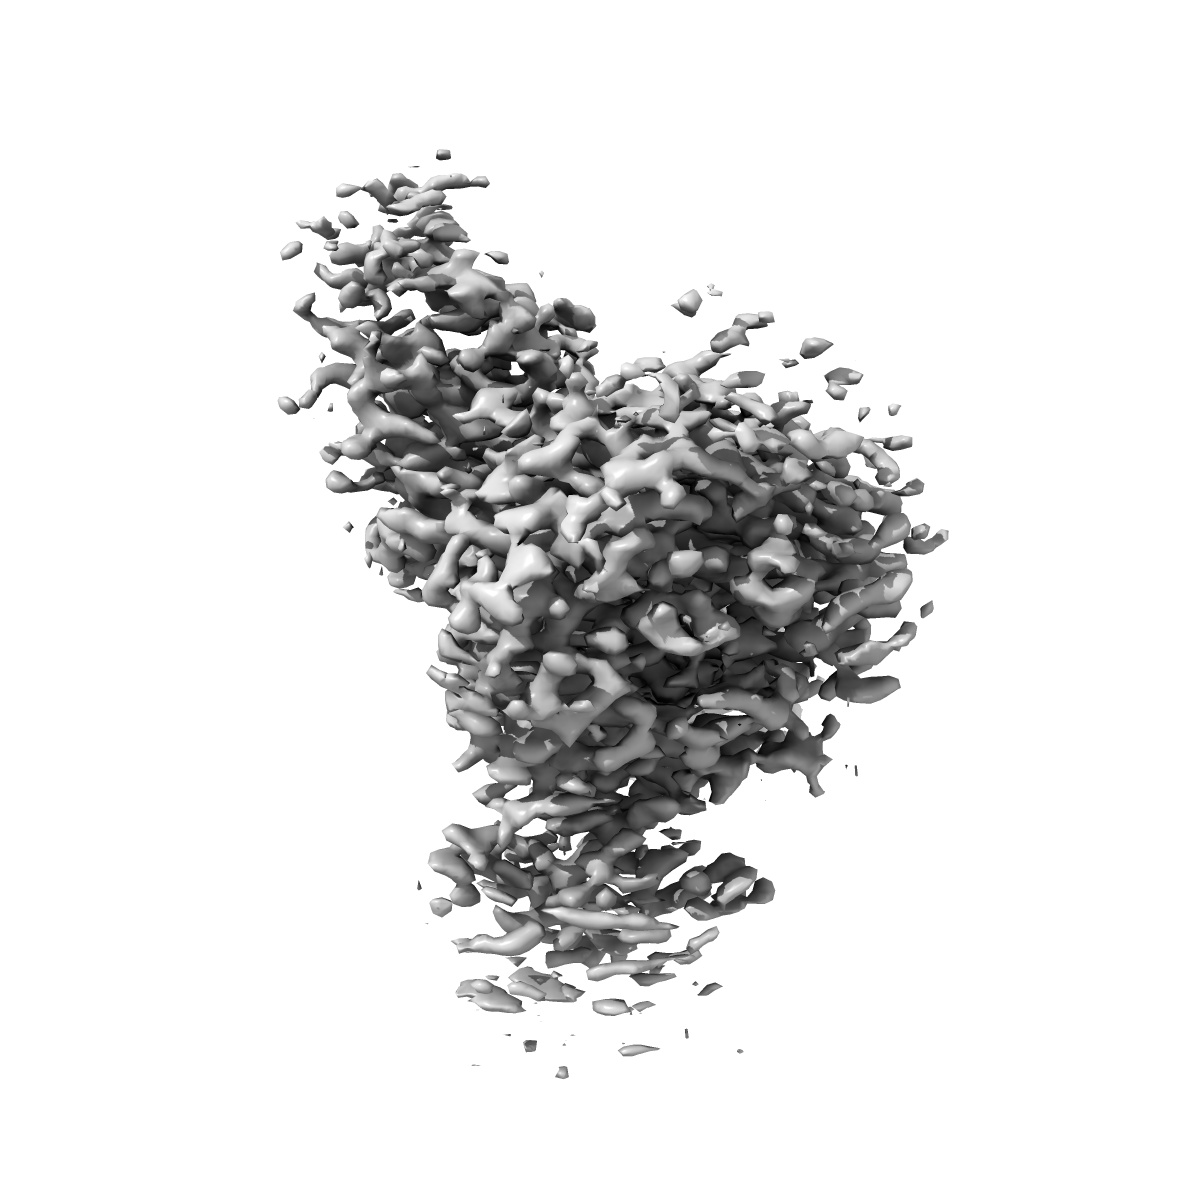

EMD-44643

Cholecystokinin 1 receptor (CCK1R) sterol 7M mutant, Gq chimera (mGsqi) complex

Single-particle2.51 Å

Sample: Complex of CCK1R (sterol 7M mutant) bound to miniGs (Gq, Gi chimera), G-beta1, G-gamma-2 and CCK8s.